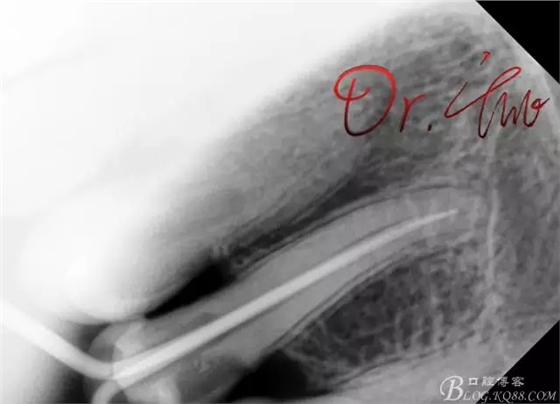

拍片確定長度

第一次試主尖